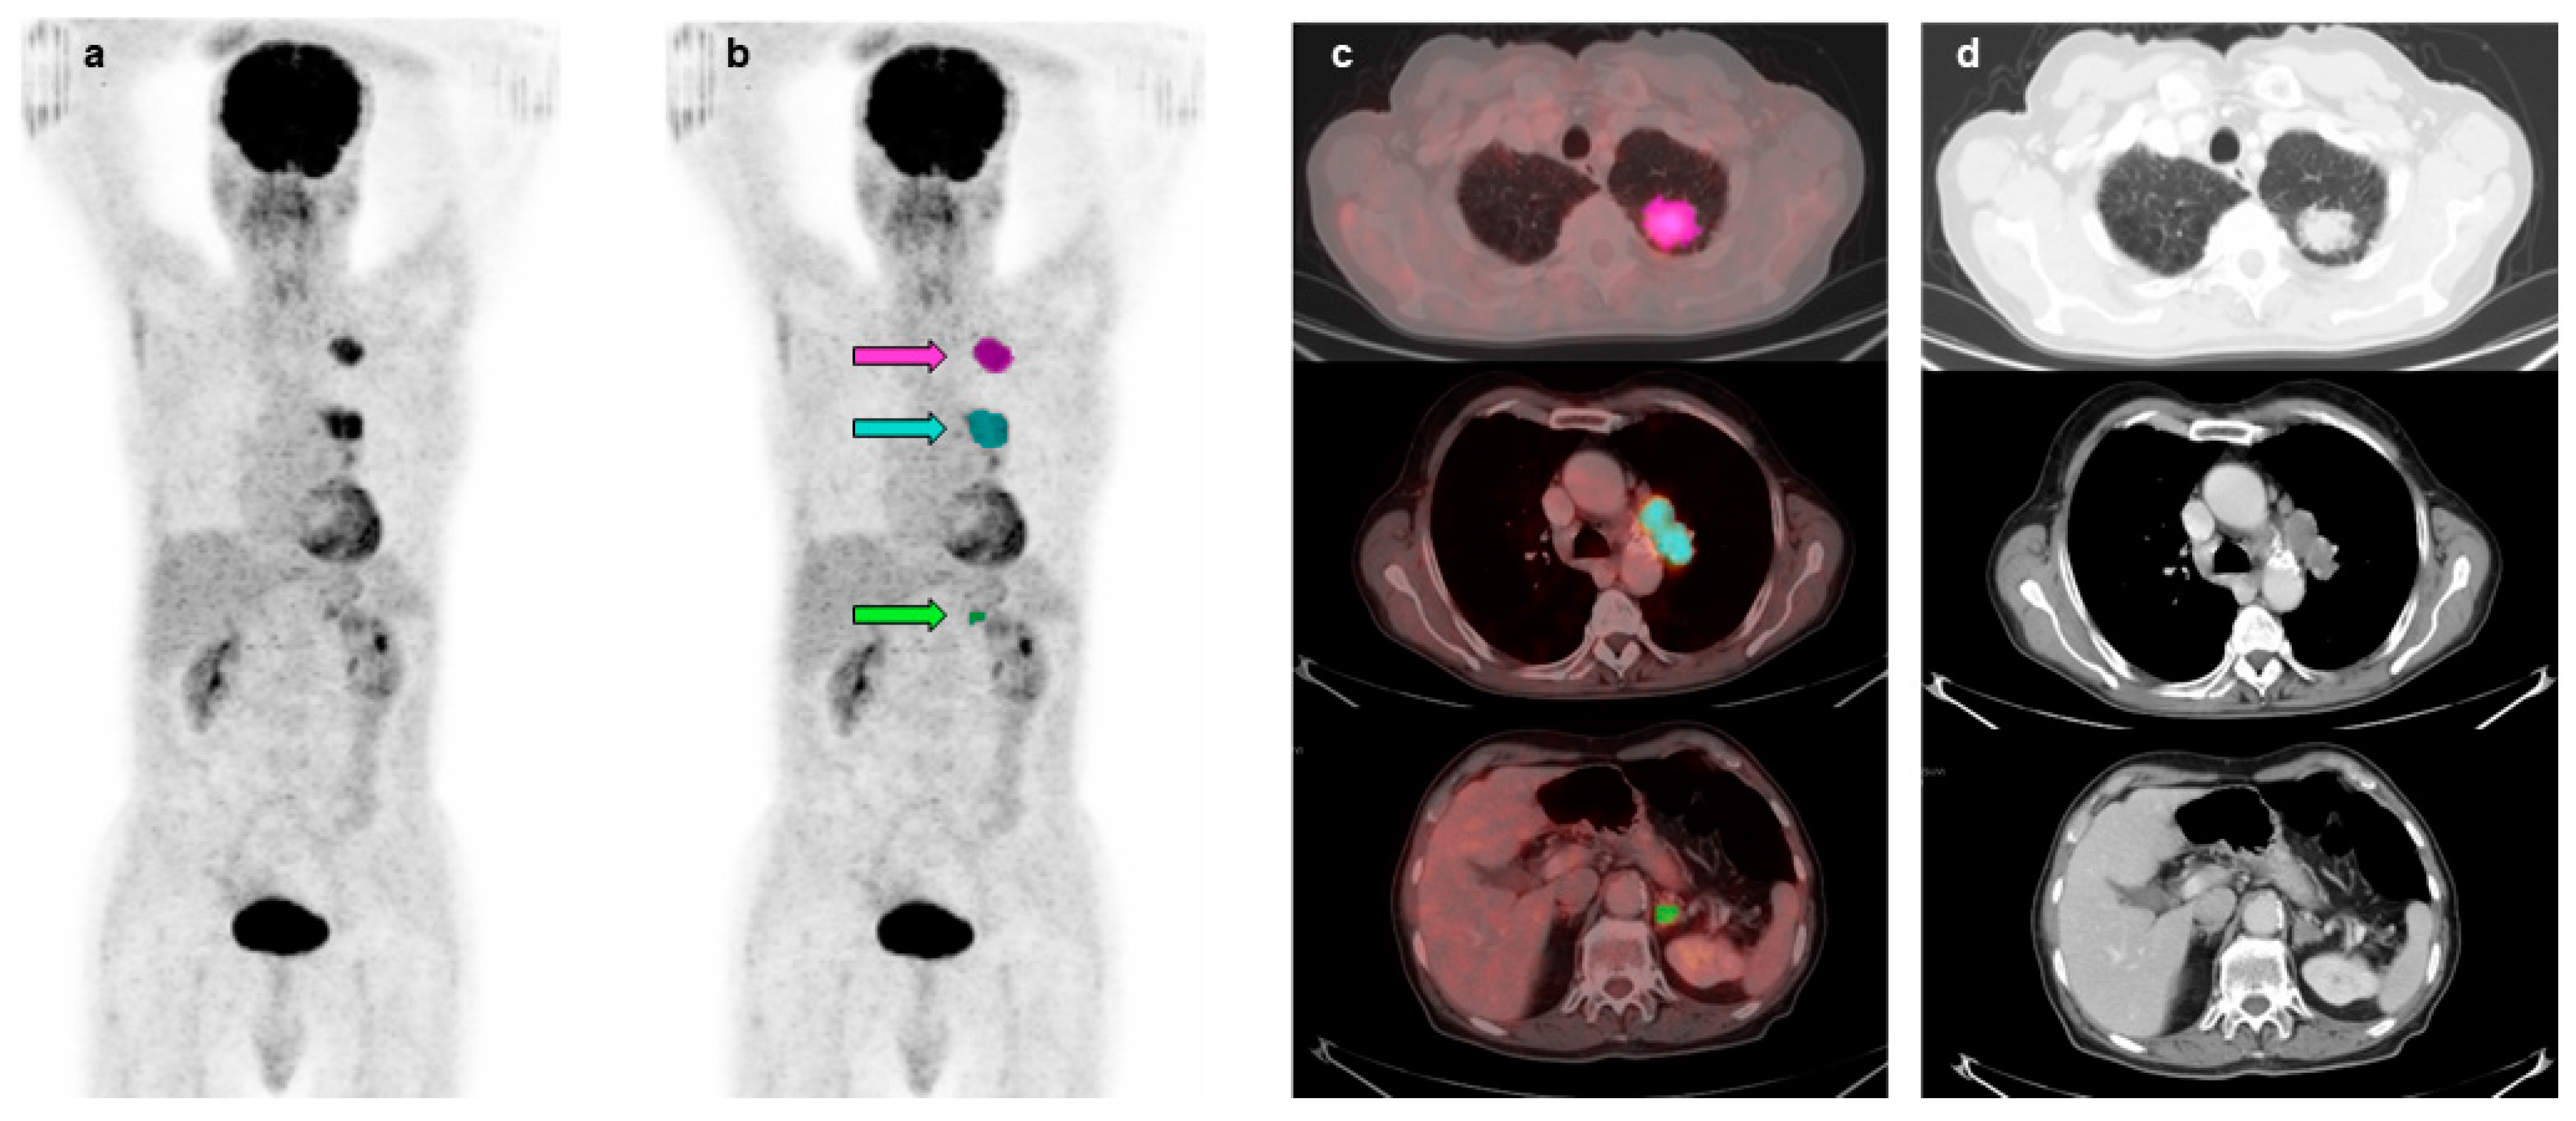

| Lesions | N° | SUVmax | SUVmean | CoV | |||

|---|---|---|---|---|---|---|---|

| Mean ± SD | Median | Mean ± SD | Median | Mean ± SD | Median | ||

| Primary tumors | 84 | 12.17 ± 5.86 | 11.63 | 5.44 ± 2.04 | 5.05 | 0.36 ± 0.13 | 0.38 |

| Regional nodes | 48 | 10.97 ± 6.96 | 10.29 | 4.67 ± 1.85 | 4.35 | 0.36 ± 0.14 | 0.36 |

| Extraregional nodes | 17 | 14.22 ± 10.41 | 11.08 | 5.40 ± 2.11 | 5.14 | 0.42 ± 0.18 | 0.41 |

| Liver metastases | 9 | 9.90 ± 4.67 | 9.41 | 5.12 ± 1.48 | 5.50 | 0.30 ± 0.14 | 0.23 |

| Bone lesions | 23 | 10.68 ± 5.21 | 9.54 | 4.46 ± 1.00 | 4.35 | 0.37 ± 0.17 | 0.35 |

| Other distant metastases | 13 | 10.36 ± 3.82 | 10.57 | 4.79 ± 1.19 | 5.16 | 0.34 ± 0.13 | 0.38 |